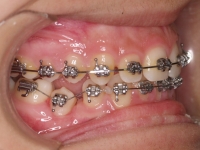

Premolar mandibular incluido + fenestración

45 incluido